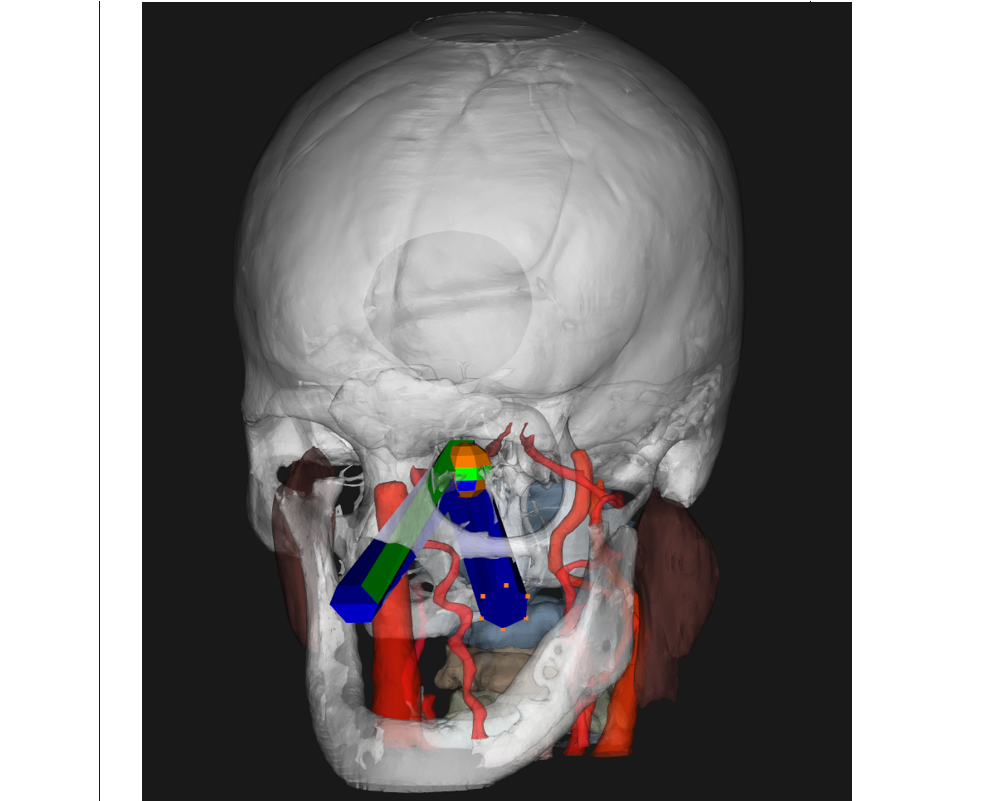

Skull base navigator is a tool we created that allow surgeons to interactively plan surgeries, practice surgery preoperatively, as well as quantitatively review surgical procedures.

Automatic Surgical Planning.

We identified the key metrics for Sinus and Skull Base Surgeries and use them to automatically plan surgeries.

We added modules to skull base navigator to provide intraoperative guidance and warning to surgeons, and allow surgeons to quantitatively review surgeries.

A self-developed system guides surgeons with detailed preoperative plans. The system consists of an electromagnetic navigation component, a graphic user interface component, and a real-time warning component.